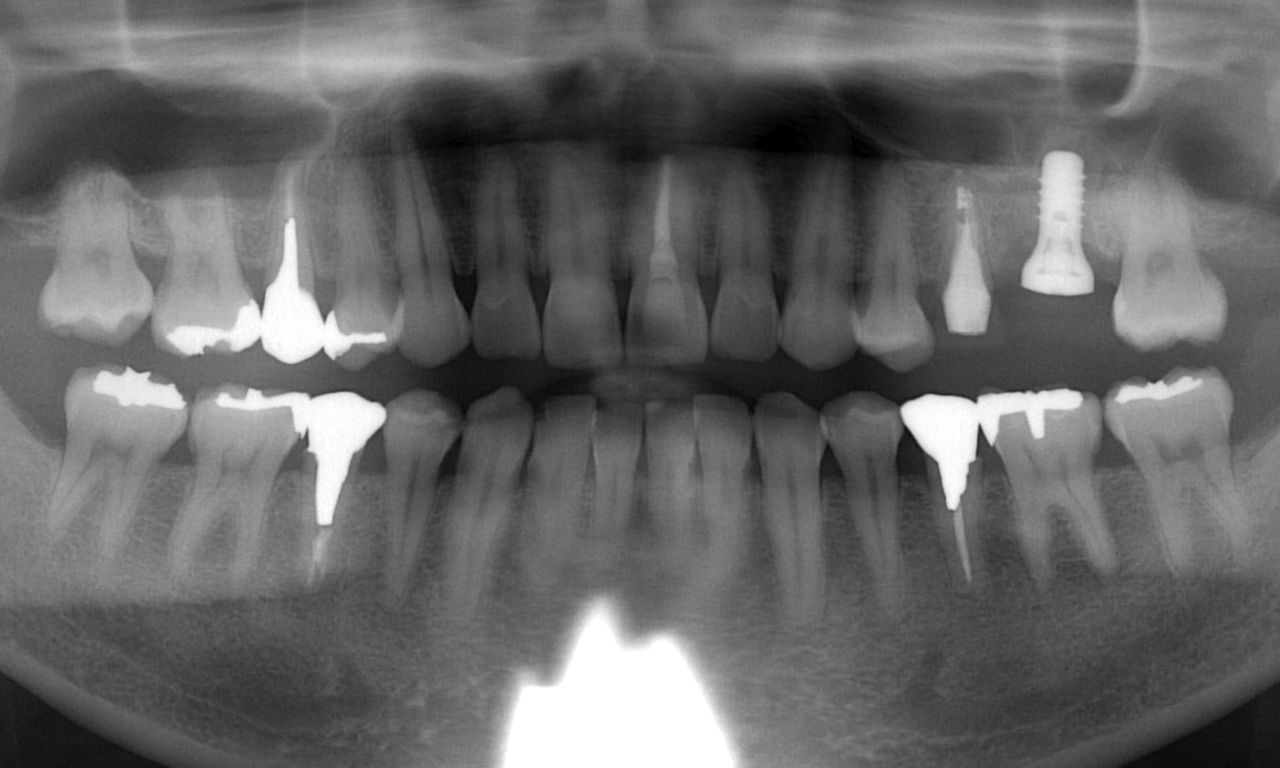

先程と同じように抜歯後の骨吸収の状態を線で書いてみましょう。

骨吸収の状態を線で書いたのが以下のレントゲンになります。

青線が骨吸収を起こす前の骨の位置です。

赤線は、現在の骨の位置です。

さらに分かりやすくするために 骨吸収部位を赤色の領域で表します。

さらに問題があったのが、上顎洞の存在です。

上顎洞の問題が起こっていました。

以下の緑線は上顎洞という空洞です。

緑線の内側は空洞なのです。

骨ではありません。

ただの 穴 です。

これも さらに分かりやすくするために、上顎洞 を緑色で表示します。

骨吸収と上顎洞の存在のためにインプラントを埋入するための骨の高さが非常に少なかったのです。

欠損部の手前の部分は、比較的骨の高さが存在していました。

しかし、奥の部位には、骨吸収が大きいため インプラントを埋め込むための骨の高さが存在していない状態でした。